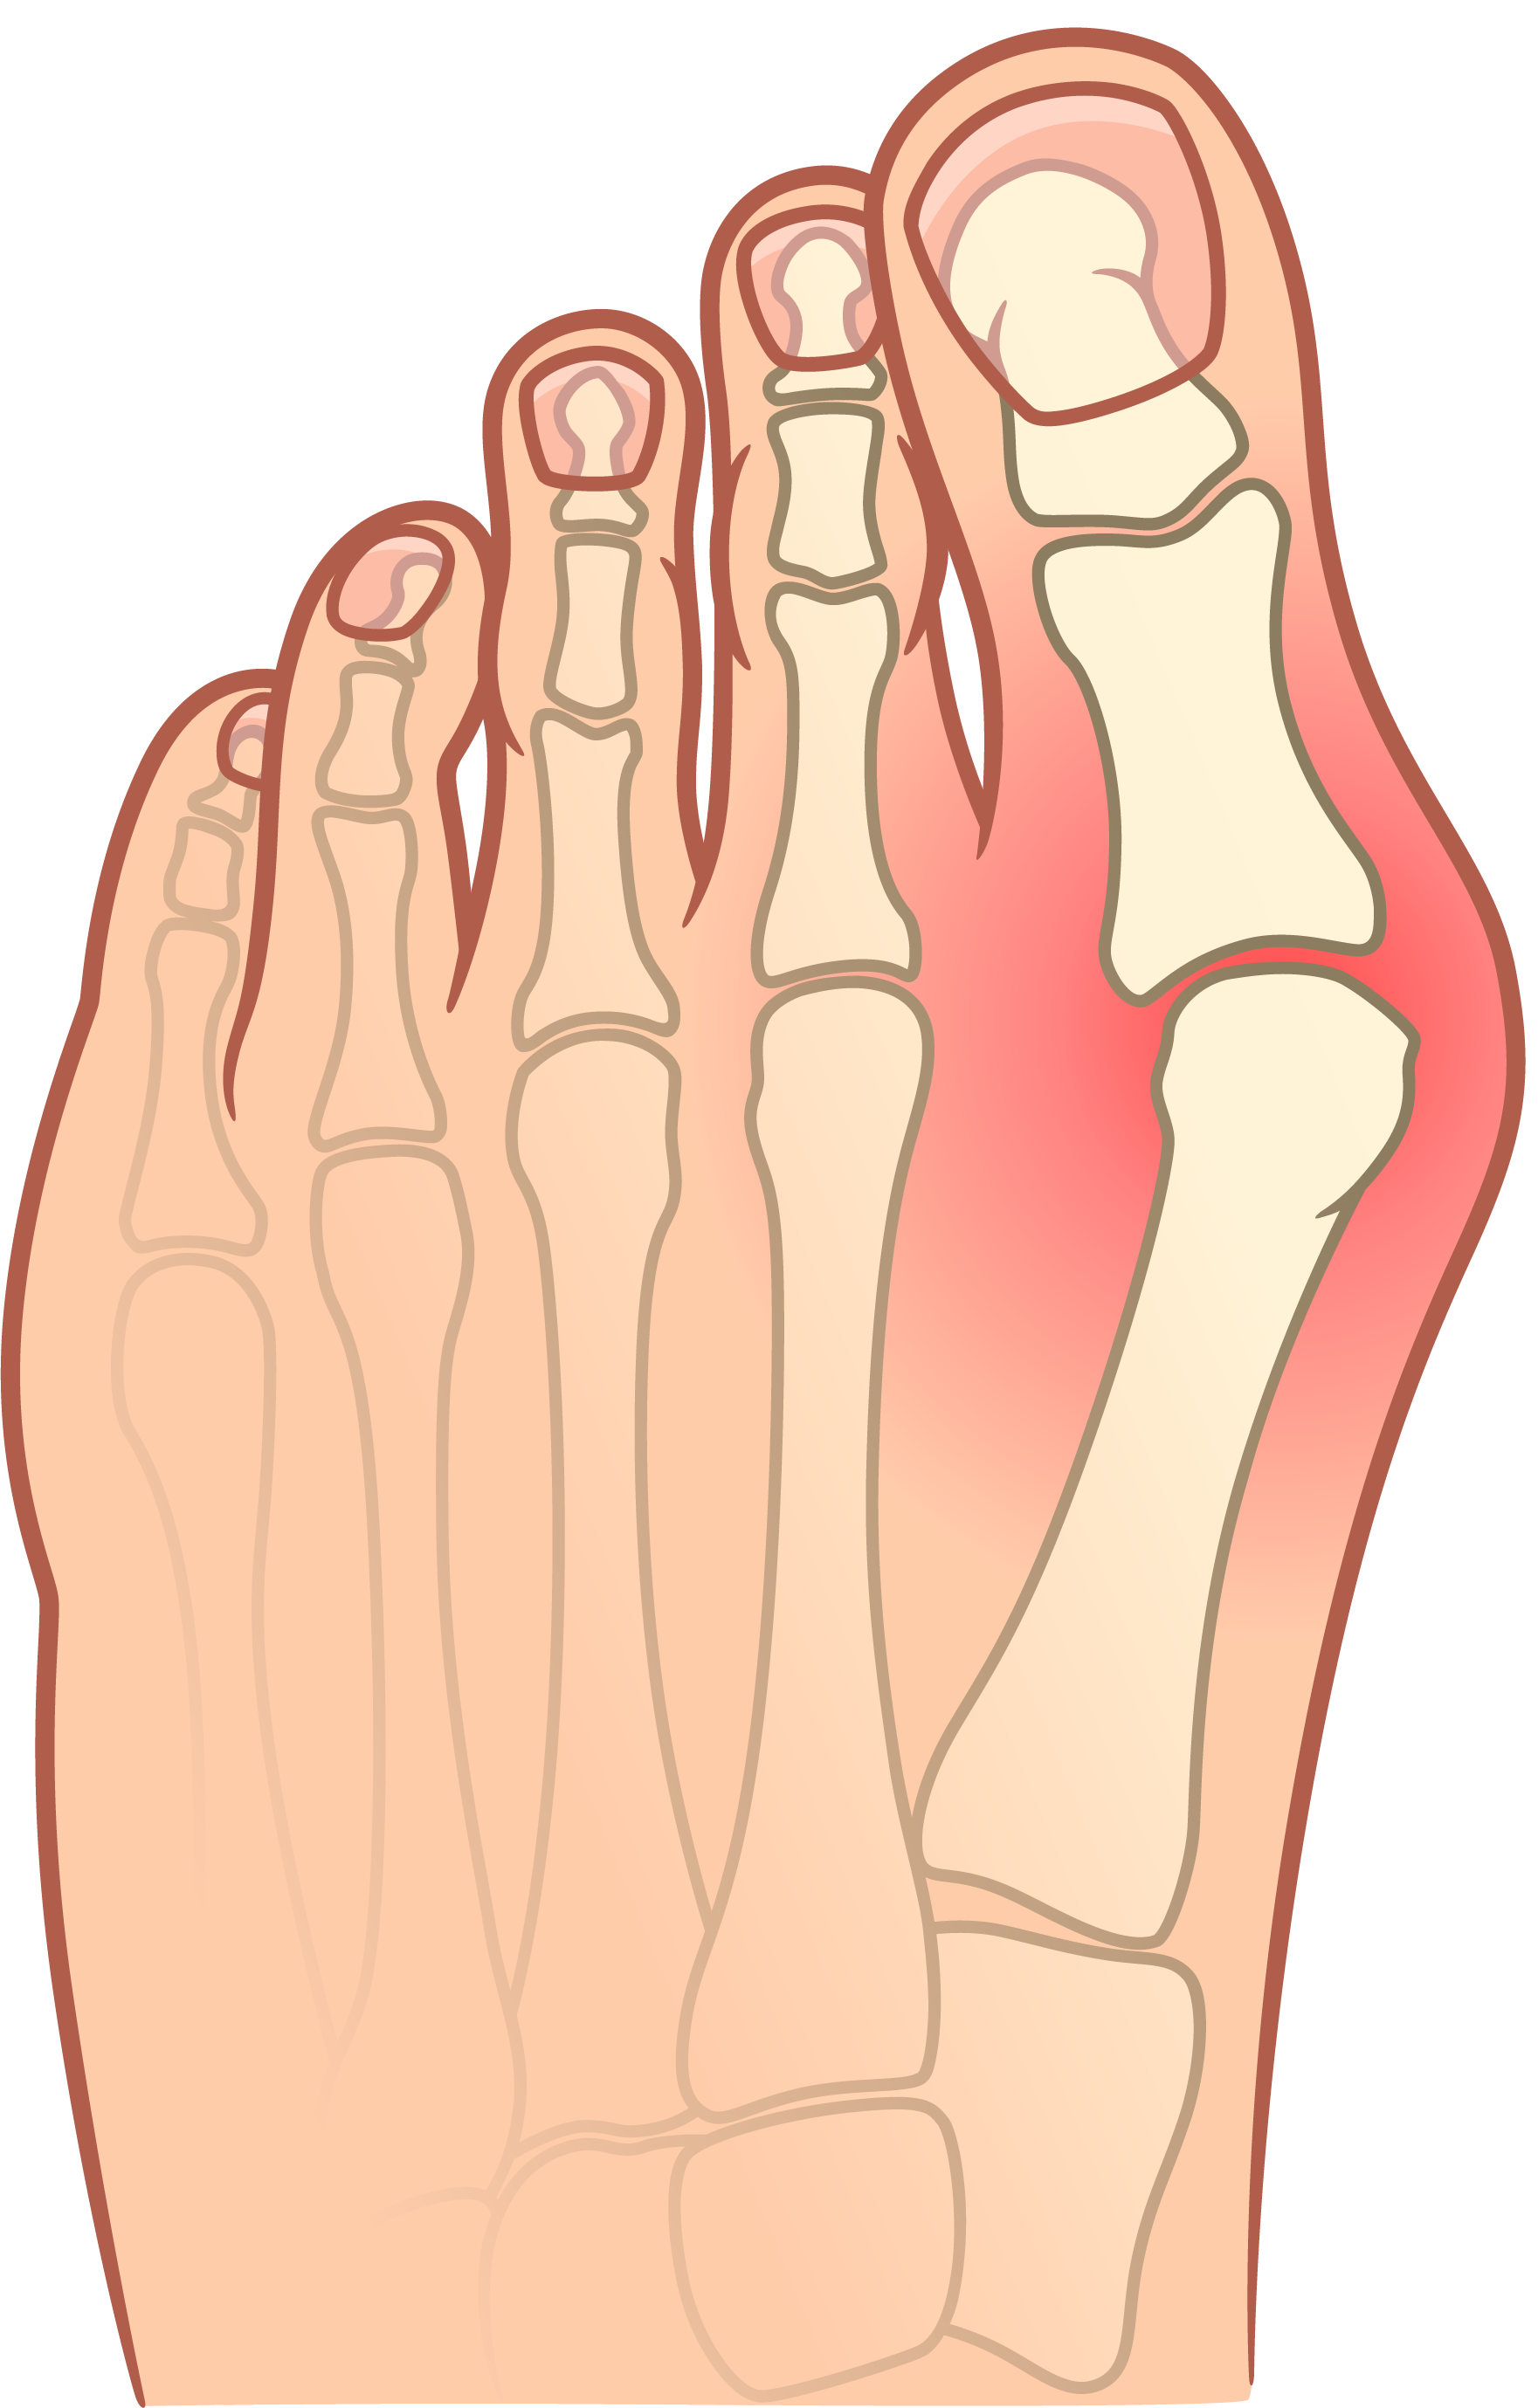

- imate čukljeve (haluks valgus),

- teško hodate zbog čukljeva,

- žalite se na bolove u stopalima, gležnjevima, koljenima,

- imate kurje oči, žuljeve, ogrebotine i rane na stopalima,

PRIJE

Stopalo iskrivljeno zbog čukljeva - izbočene kosti, oticanje i oguljenja uzrokuju bol i otežavaju hodanje.

POSLIJE

Prsti su povratili pravilan položaj, a bolne i neestetske deformacije metatarzalnih kostiju nestale su.